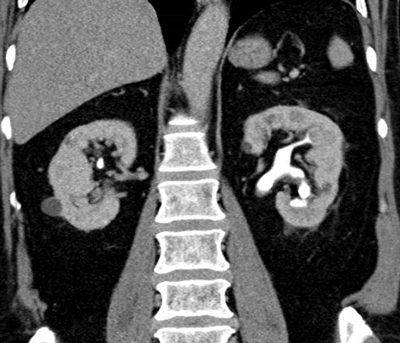

CT can be used to assess the internal structure of calculi, which is best seen using bone windows [4] compared with abdominal windows where the stone may appear homogeneous. Some studies have shown that heterogeneous calculi are more fragile leading to better fragmentation with treatment, as the irregularities seen within the calculus act as focal spots for shock wave treatment, leading to better fragmentation of the stone [5] (Figure 3).

Figure 3a: Abdominal windows stone fragility.

Figure 3b: Bone windows stone fragility.